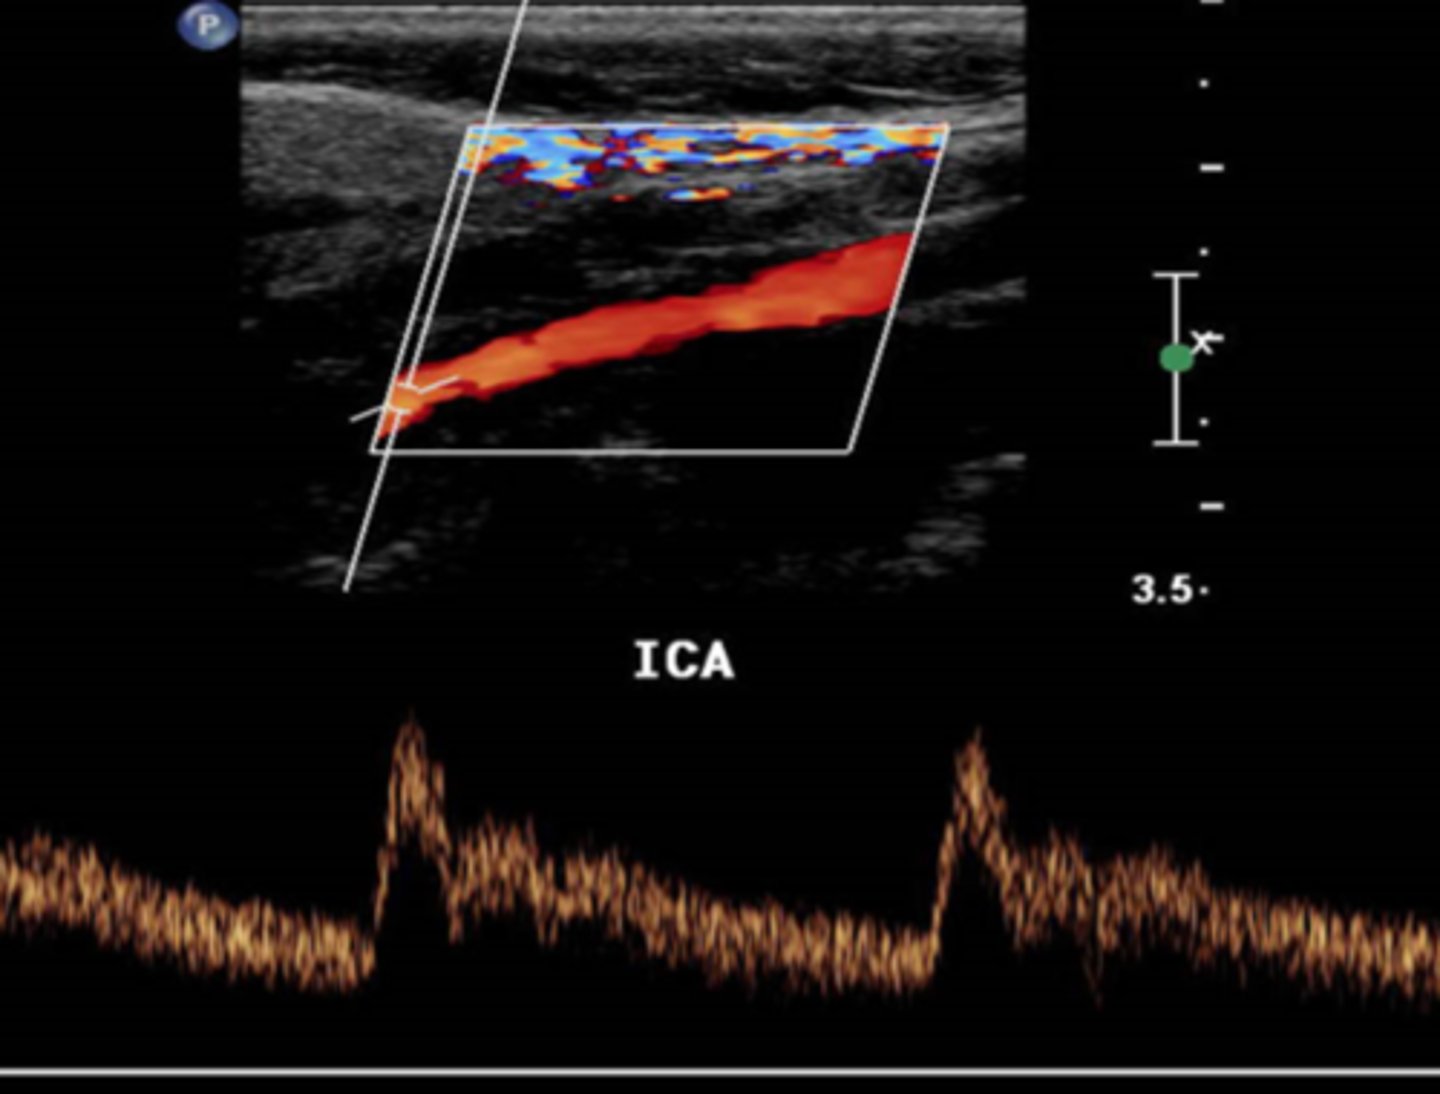

It is extremely important for sonographers to recognize the difference between blood flow patterns associated with the Internal Carotid Arteries that bring blood to the brain and the External Carotid Arteries that bring blood to the face and scalp. What percentage of blood from the Common Carotid Artery (CCA) branches to the ICA?

10%

20%

50%

80%

It is extremely important for sonographers to recognize the difference between blood flow patterns associated with the Internal Carotid Arteries that bring blood to the brain and the External Carotid Arteries that bring blood to the face and scalp. If the capillary vascular bed that receives blood from a vessel is said to be "low resistance", which of the statements below best describes the characteristics of blood flow.

blood flow is forward during diastole, but reversed during systole

blood flow is forward during systole, but reversed during diastole

blood flow is forward during both systole and diastole

blood flow is reversed in both systole and diastole

It is extremely important for sonographers to recognize the difference between blood flow patterns associated with the Internal Carotid Arteries that bring blood to the brain and the External Carotid Arteries that bring blood to the face and scalp. If a sonographer were to describe the flow in a high resistance vascular bed and how that would look on a spectral Doppler waveform, the sonographer might say...

the spectral Doppler tracing accelerates to a peak in systole and then touches the baseline during diastole

the spectral Doppler tracing accelerates to a peak in systole, decelerates in diastole, but does not touch the baseline